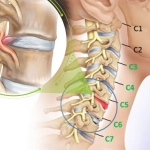

Thoái hóa đốt sống cổ là tình trạng bệnh lý do thoái hóa của các xương, sụn, các cơ dây chằng, các phần mềm và bao hoạt dịch của đốt sống. Bệnh thoái hóa đốt sống cổ thường có các biểu hiện sớm thường gặp là:

Thoái hóa đốt sống cổ là do thoái hóa hệ thống xương cột sống vùng cổ, gây bởi các nguyên nhân khác nhau như chế độ dinh dưỡng, công việc, lao động, hoạt động, tuổi tác. Nó là quá trình gây bệnh ở các đốt sống và xương đốt sống cổ, đầu tiên là sự suy giảm mật độ ở các đốt xương, cộng thêm sự hư khớp ở các thân đốt, đĩa liên đốt tới các màng, dây chằng, hậu quả là tình trạng thoái hóa các đốt sống cổ, thoát vị đĩa đệm cột sống cổ gây đau vùng cổ xuất hiện, nhất là khi hoạt động hoặc tác động vùng cổ. Nói cách khác, đây là bệnh của quá trình lão hóa tự nhiên cùng với sự chăm sóc xương khớp chưa đầy đủ kết hợp với 1 trong các yếu tố thuận lợi tác động. Bởi vậy, bệnh này rất thường gặp ở độ tuổi trung niên, trong khoảng từ 30-50 tuổi.